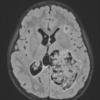

NEOPLASMS (NON-GLIAL NON-NEURONAL)

Choroid plexus papilloma (6)